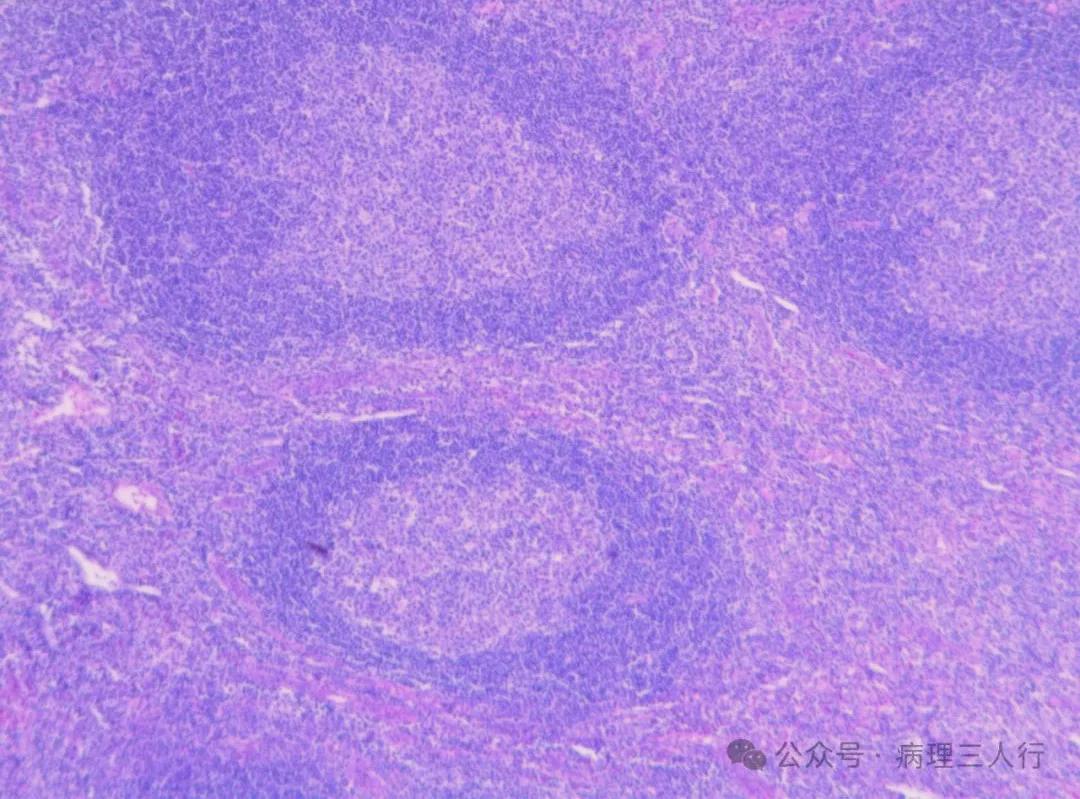

病例221-Kimura病

又称木村病,以血管淋巴组织增生伴有嗜酸性粒细胞增多为特征。

镜下:

1.不同程度的滤泡增生及生发中心形成;

2.皮质旁和滤泡内明显的嗜酸性粒细胞浸润,并可形成嗜酸性微脓肿;

3.滤泡生发中心内见嗜酸性物质沉积;

4.可见薄壁小血管增生。